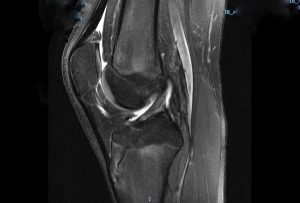

Imagem de ressonância magnética com LCA normal em adolescente